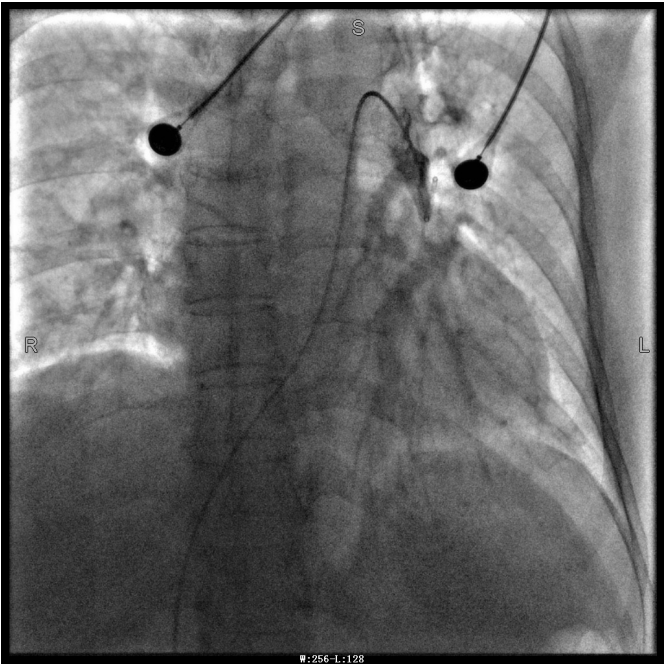

譚婆婆今年已經(jīng)72歲了,因“突發(fā)意識障礙2次”到璧山區(qū)人民醫(yī)院神經(jīng)內(nèi)科治療。譚婆婆沒有基礎(chǔ)心臟病病史,但近段時間活動耐量明顯下降,稍做活動就出現(xiàn)呼吸困難。入院后查BNP及心臟彩超均未提示明顯異常,查D二聚體明顯升高,經(jīng)心血管內(nèi)科周波醫(yī)師會診后轉(zhuǎn)入科室繼續(xù)治療。在心血管內(nèi)科主任、內(nèi)科學(xué)(心血管病)博士于長青的指導(dǎo)下,周波醫(yī)師成功完成醫(yī)院首例“一站式”微創(chuàng)介入手術(shù)。在影像中,可以清晰地看到堵塞的血管經(jīng)溶栓治療后,重新暢通無阻,流動起支撐生命的血液。

第三章未標(biāo)注圖像為術(shù)后圖像